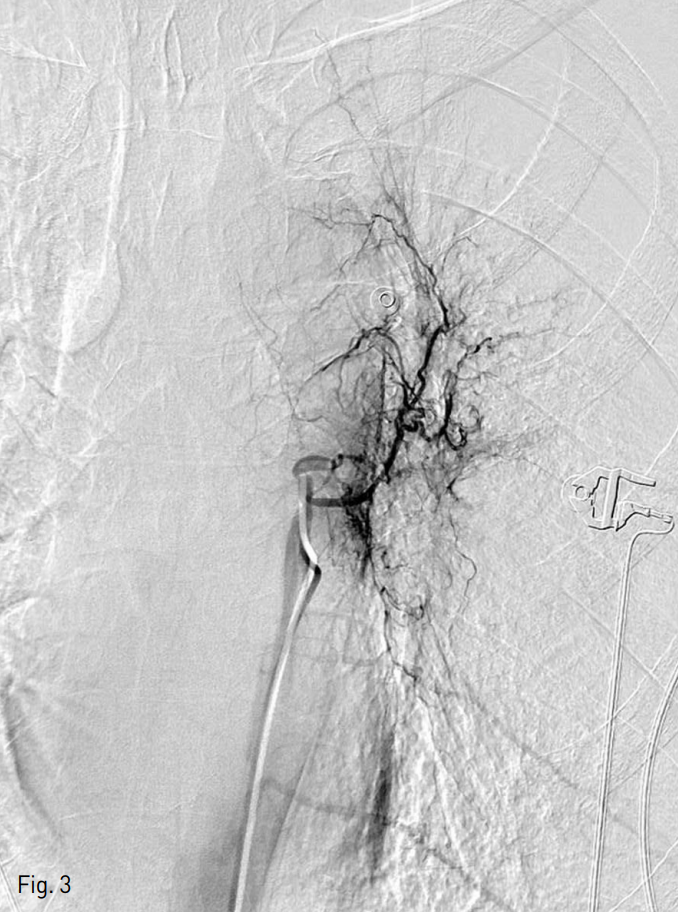

Fig. 3

The left bronchial angiograms show arterial hypertrophy and shunting of pulmonary artery.